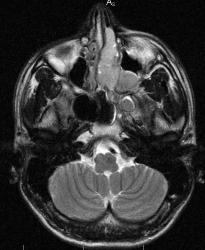

В последнее время на сайте много сообщений о патологии такой локализации. По закону парности и ко мне пришел пациент с направлением "Исключить опухоль орбиты". Мужчина 1982 г.р. жалуется на значительное снижение зрения на левый глаз. Зрачок расширен, движения глаза ограничены.

Большого объёма негомогенная масса, скорее всего опухоль, занимает слева полностью решетчатый лабиринт (видимо отсюда и исходит), а также частично полость носа, гайморову, клиновидную и лобную (полностью?) пазухи, проникает в глазницу, сдавливая и оттесняя её содержимое вперёд и кнаружи.